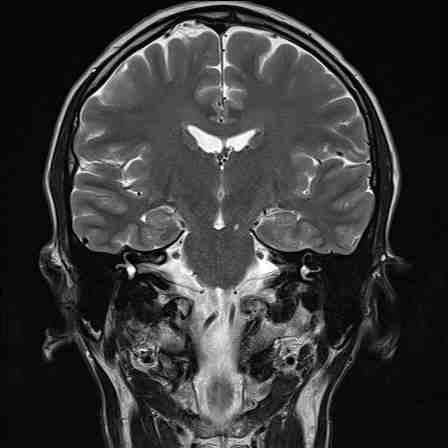

Magnetresonanztomografie

MRT

Das Diagnosezentrum Omega arbeitet mit einem 1,5 Tesla Hochleistungs-MRT-Gerät der letzten Generation (Siemens SolaFit).